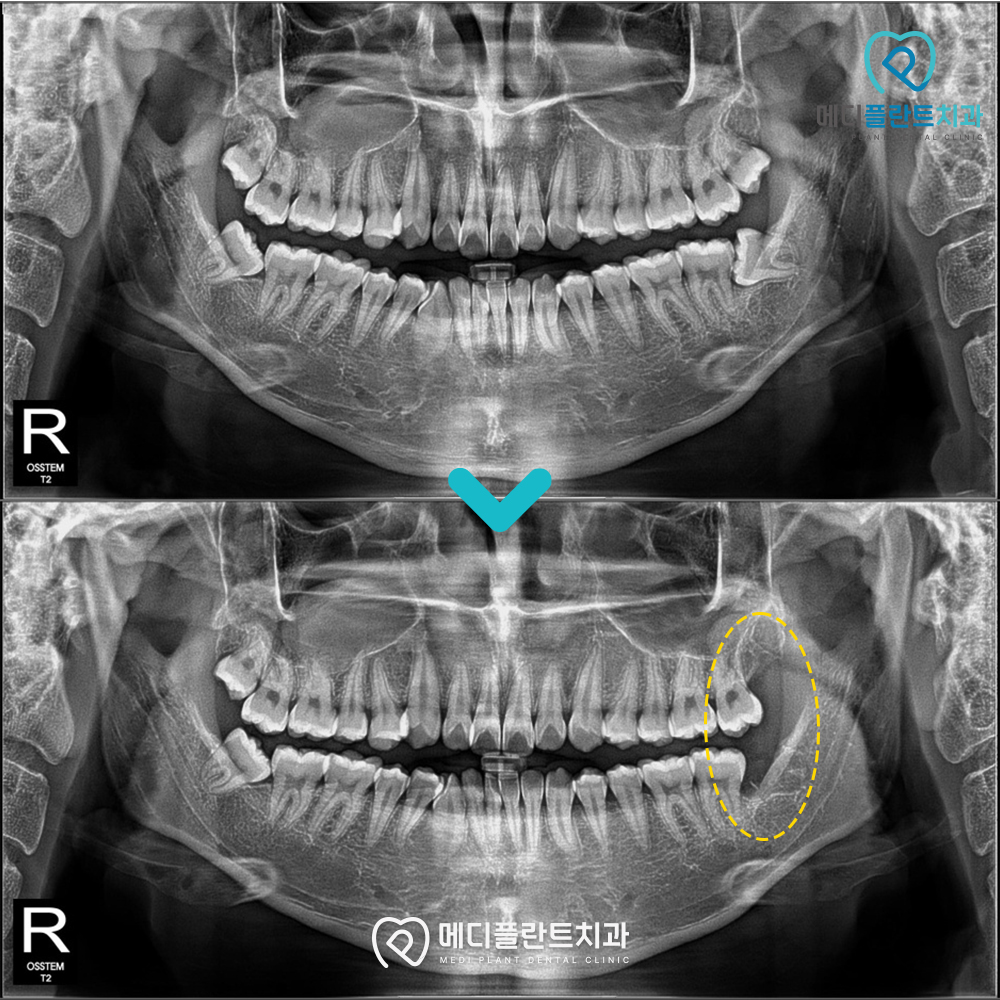

파노라마 촬영을 통해 확인한 결과,

사랑니가 정상적인 방향이 아닌

앞쪽 어금니 방향으로 기울어진 상태로

자라고 있는 양상을 보였습니다.

이처럼 비스듬히 자라는 사랑니는

인접 치아와의 사이에 음식물이 쉽게 끼고

위생 관리가 어려워지면서

충치나 잇몸 염증으로 이어질 가능성이 있는데요.

또한 시간이 지나면서

주변 치아의 뿌리까지 영향을 줄 수 있어

빠른 발치를 고려해야 하는 상태였습니다.

이에 따라 발치 전

신경관과의 거리와 치아의 위치,

각도를 정밀하게 확인하였으며

추가적인 영상 검사를 통해

안정적인 시술이 가능하도록 계획을 수립하였습니다.